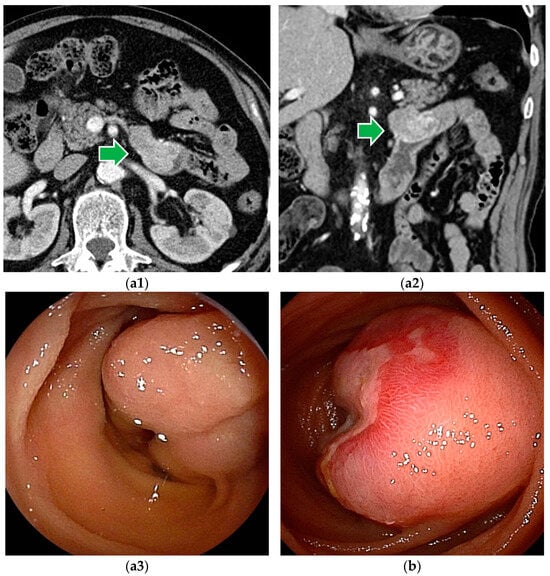

Figure 3.

Malignant lymphoma: (a) Follicular lymphoma is characterized by aggregations of large and small white granules. The lesions are distributed focally from the duodenum to the jejunum. (b) Rarely, it may be a form of concentric stenosis with ulceration. (c1,c2) Diffuse large B-cell lymphoma (DLBCL) often shows an ulcerated or polypoid morphology, and the biopsy should be taken from the ulcer bed rather than from the edges. CT revealed a wall-thickened intestine with a dilated lumen. DBE showed an ulcerated lesion.

Although endoscopic findings of malignant lymphomas vary by histologic type (Figure 3), a definitive histopathologic diagnosis can be made by biopsy in most cases. Based on the histopathologic diagnosis, lymphomas can be treated with chemotherapy [26,27]. However, in cases of bleeding or obstructive symptoms, chemotherapy is given after surgical treatment.